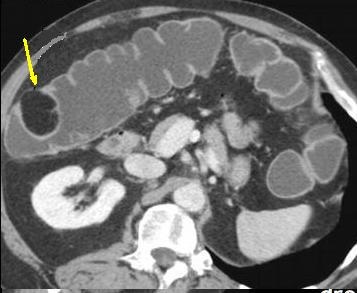

certaine cas de enterite inflammatoire compliquee . - Image

radiologique d'une coloscanner a

l'eau c'est la technique TDM avec une opacification du

colon a l'eau tiede ( comme une lavement baryte ) a l'aide

une sonde rectale . L'exploration et les exposes represence

apres distension colique a l'eau tiede avec injection de

contrast iode hydrosoluble

par voie intraveineuse :

Image d'une polyp du colon (

fleche rouge ) . Colos scanner a eau en coupe axiale

. Cette technique peu elimine des polyps de plus de

7mm |

Image d'une masse arrondie a

hypodense situe au angle colique droit . Aspect

d'une lipome du colon droit . Image radiologique de

coloscanner a l'eau |

|

La difference de coloscanner

a l'eau et la TDM de sans preparation est il n'a pas

d'air dans le colon et image de la paroi du colon de

la lesion est plus net ( plus hyperdense ) que la

TDM normale |